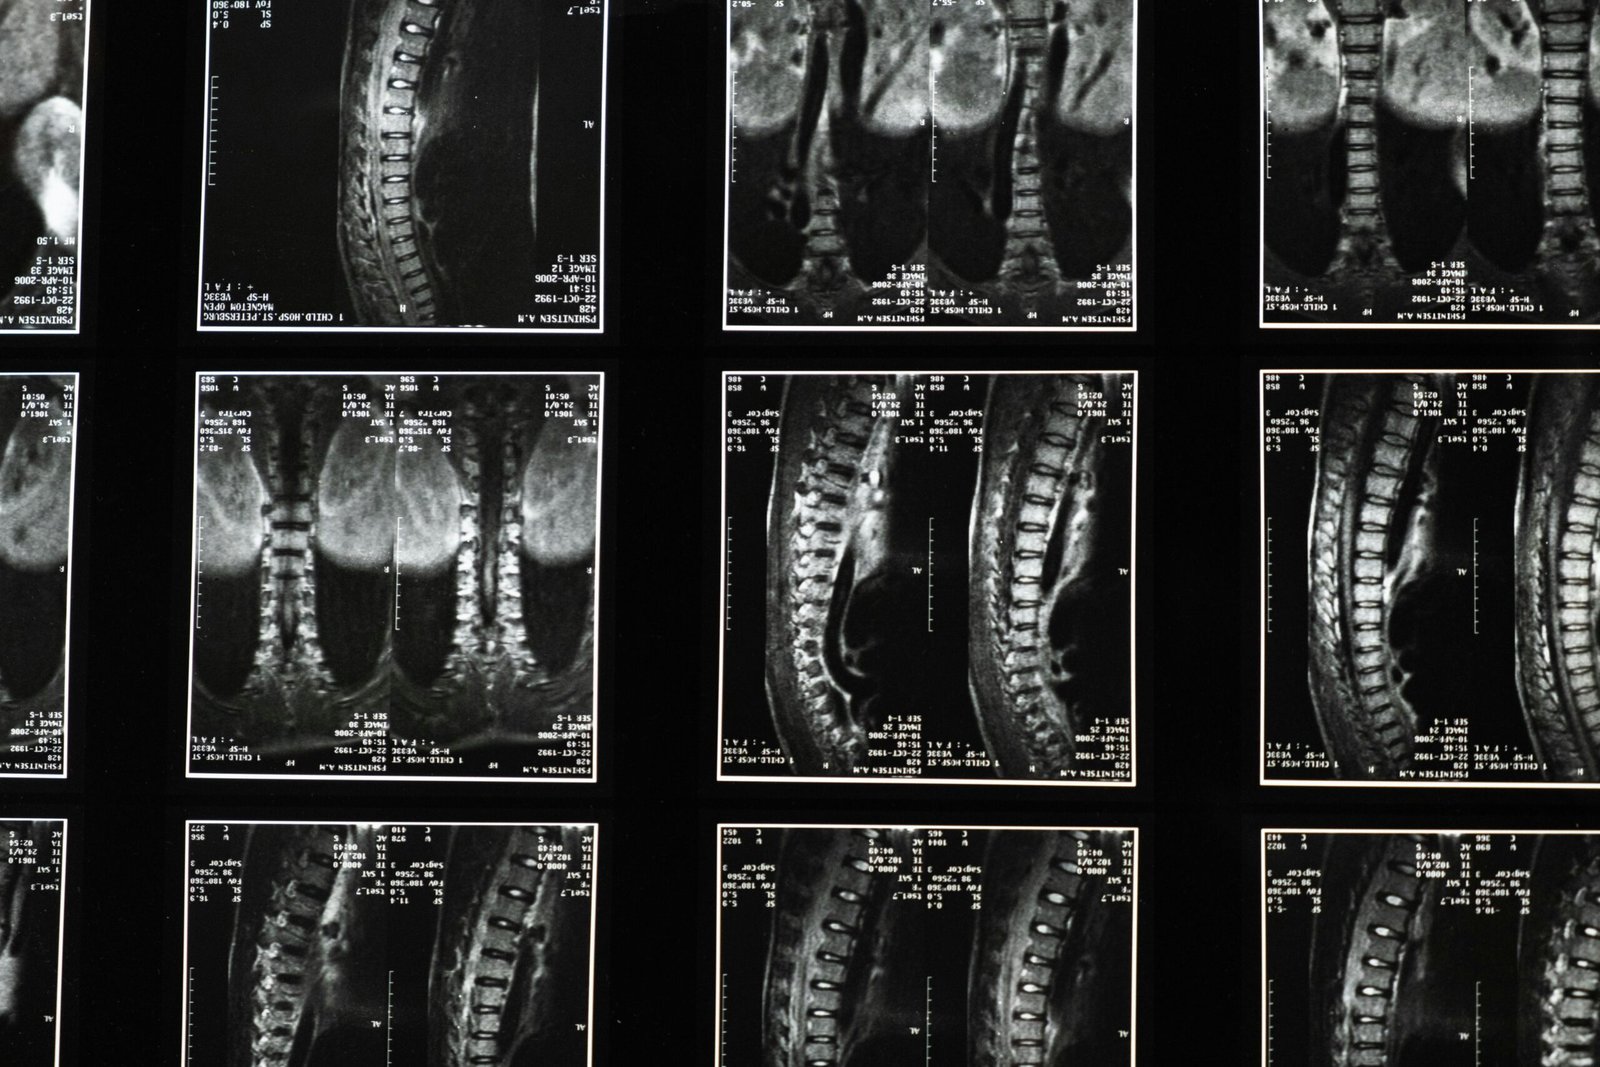

Η ιατρική φροντίδα έχει προχωρήσει πολύ πέρα από την εποχή που ο γιατρός βασιζόταν μόνο στην κλινική εικόνα και στις περιγραφές του ασθενή. Σήμερα, οι απεικονιστικές εξετάσεις έχουν καθοριστικό ρόλο, γιατί επιτρέπουν την πιο ακριβή χαρτογράφηση ενός προβλήματος πριν αποφασιστεί η κατάλληλη θεραπεία. Ανάμεσα σε αυτές, η μαγνητική τομογραφία κατέχει ξεχωριστή θέση. Ο βασικός λόγος είναι η υψηλή διαγνωστική της αξία. Με τη βοήθειά της μπορούν να αξιολογηθούν με μεγάλη λεπτομέρεια περιοχές όπως ο εγκέφαλος, η σπονδυλική στήλη, οι μύες, οι αρθρώσεις, οι σύνδεσμοι και διάφορα εσωτερικά όργανα. Αυτό επιτρέπει στον γιατρό να εντοπίσει αλλοιώσεις, τραυματισμούς ή φλεγμονές που δεν είναι πάντα εμφανείς με άλλες μεθόδους. Η μαγνητική τομογραφία δεν είναι εξέταση που γίνεται τυχαία ή χωρίς λόγο. Συνήθως ζητείται όταν χρειάζεται μια πιο πλήρης εικόνα, ειδικά σε συμπτώματα που επιμένουν ή όταν υπάρχει ανάγκη επιβεβαίωσης μιας αρχικής εκτίμησης. Ένας αθλητής με χρόνιο πόνο στο γόνατο, ένας άνθρωπος με συχνές ζαλάδες ή κάποιος που αντιμετωπίζει προβλήματα στη μέση μπορεί να χρειαστεί αυτό το επίπεδο απεικονιστικής ακρίβειας ώστε να προχωρήσει σωστά η διάγνωση.

Σε αυτήν τη λογική, η μαγνητικη τομογραφια δεν αντιμετωπίζεται απλώς ως τεχνική πράξη, αλλά ως κρίσιμο μέρος μιας πιο στοχευμένης και ήρεμης διαγνωστικής διαδικασίας.